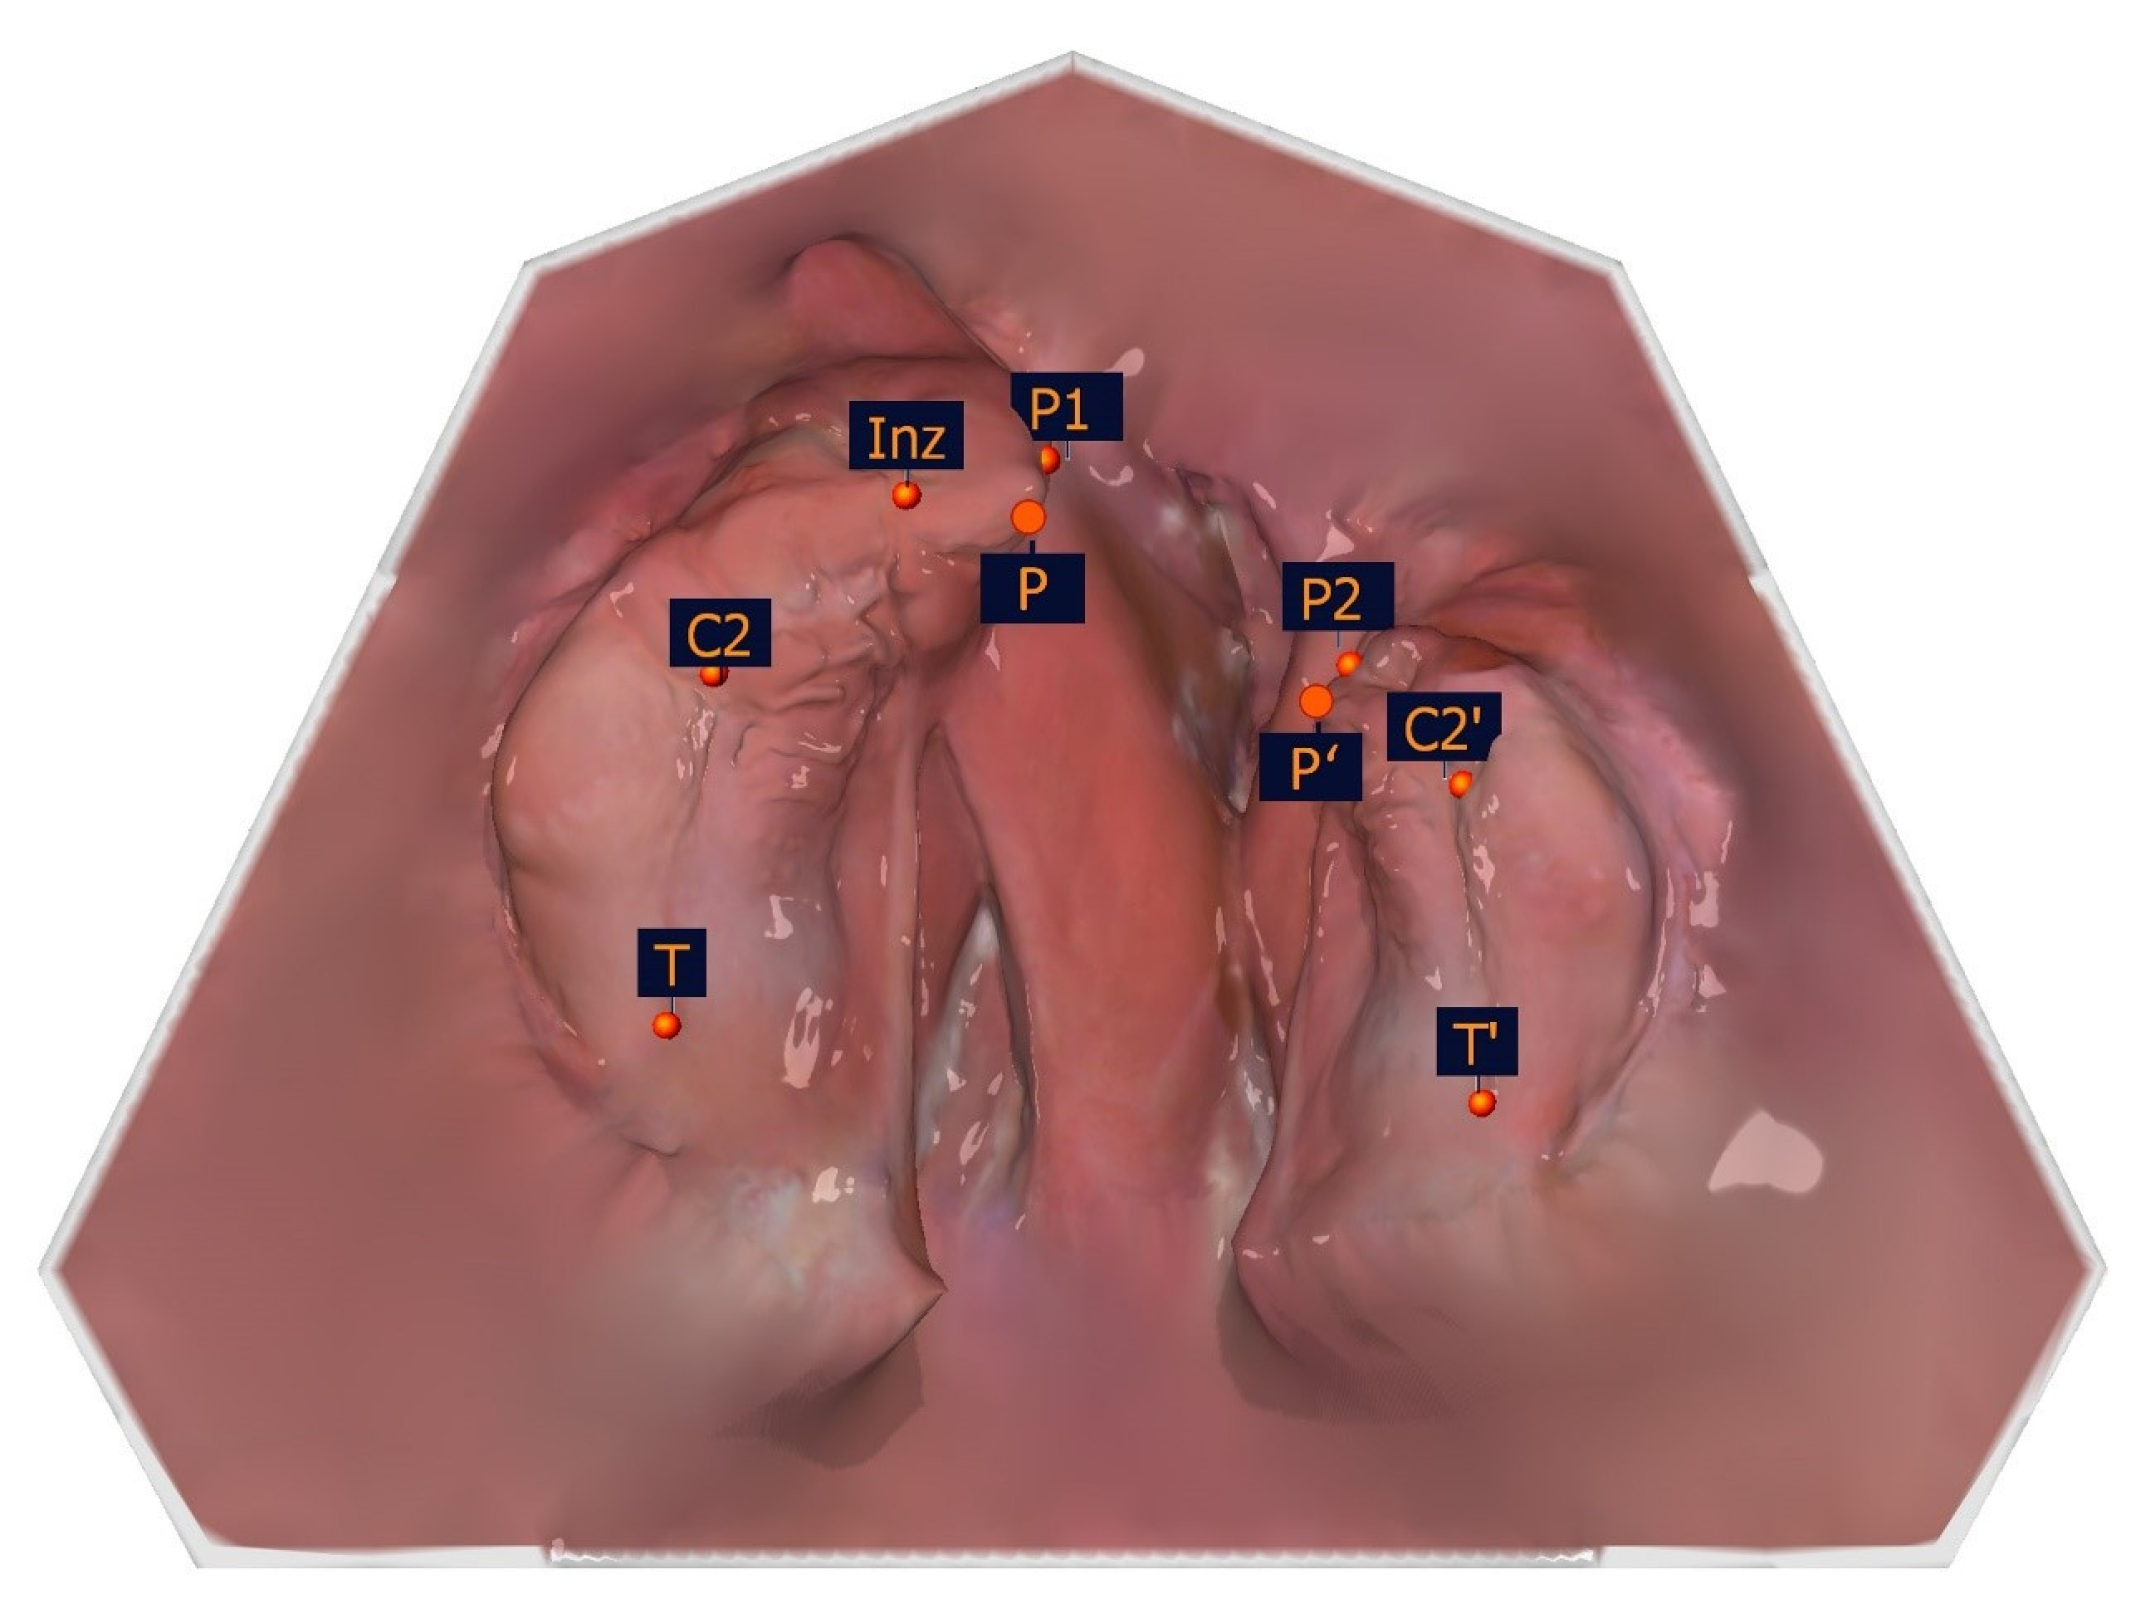

The following constructed measuring points are based on the measurement points listed in Table 1 and are shown in Table 3 and Figure 6. These and the measurement points form the basis for the subsequent distance and angle measurements.

Figure 6. Illustration of the constructed measuring points. The constructed measuring points and their description are presented in Table 3.